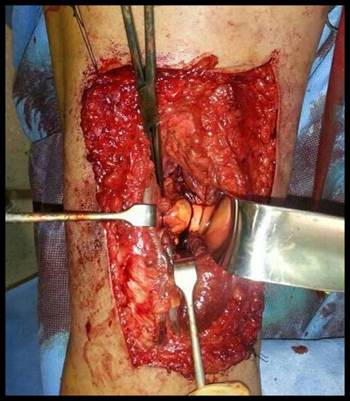

Se realiza tratamiento quirúrgico inicialmente mediante artroscopia diagnóstica, identificando lesión tumoral a través de portales artroscópicos habituales asociados a los portales postero-externo y postero-interno (ver imagen 2). Posteriormente se realiza un abordaje con capsulotomía posterior de rodilla izquierda, para llevar a cabo la exéresis de la tumoración (ver imagen 3).

Imagen 2: Tumoración (flecha) visualizada a través de portales artroscópicos posteriores de rodilla.